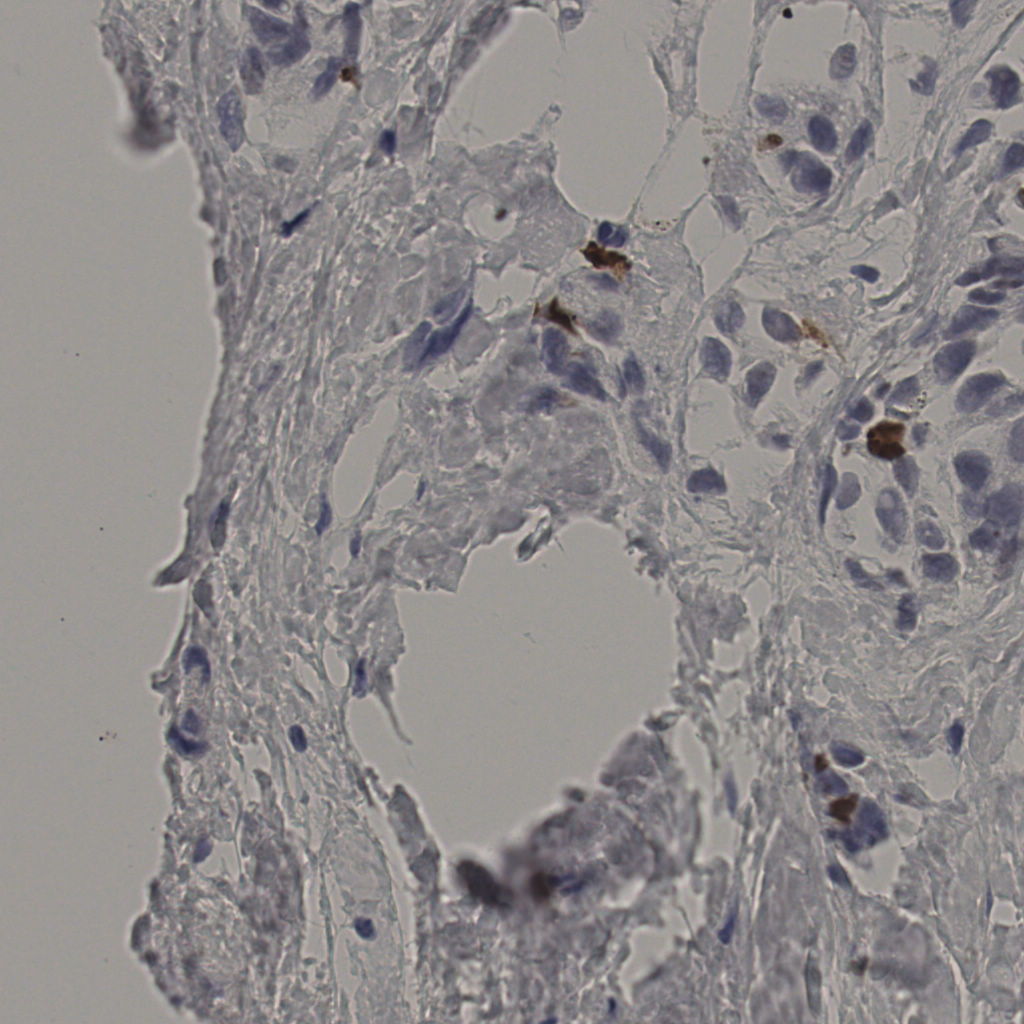

标记后

标记前